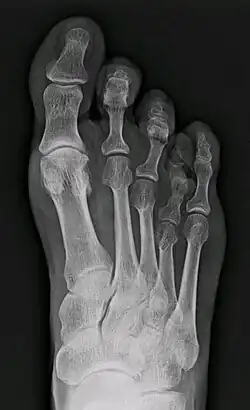

| X-ray of congenital brachymetatarsia involving fourth metatarsal bone | |

It most frequently involves the fourth metatarsal. If it involves the first metatarsal, the condition is known as Morton's syndrome. Treatment is via a number of differing surgical procedures.[3]